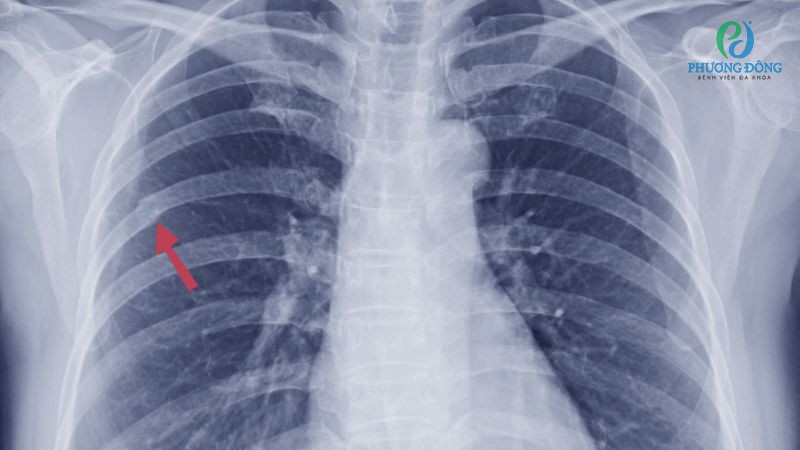

Rạn xương sườn cần từ vài tuần đến vài tháng để hồi phục hoàn toàn, có thể kéo dài nếu tình trạng gãy phức tạp hoặc bệnh nhân không tuân thủ hướng dẫn của bác sĩ. Trong thời gian điều trị, bệnh nhân cần thực hiện thêm các biện pháp hỗ trợ như giữ vị trí thoải mái và kiểm soát cơn đau để tăng tốc quá trình liền xương.

Rạn xương sườn bao lâu thì khỏi hoàn toàn?